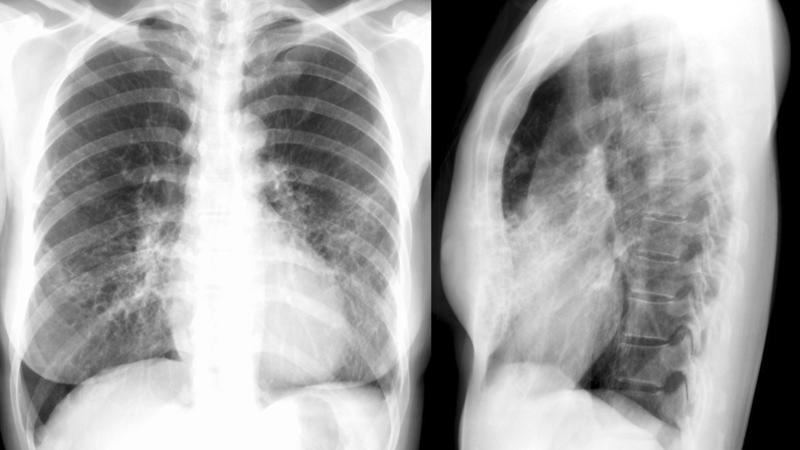

Bronchiectasis

Case 11 PA/Lat